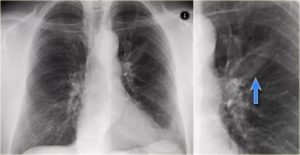

Очаг Гона на рентгенограмме выглядит как затемненное образование с резкими очертаниями. Излюбленным местом локализации признаются нижние и средние зоны органа. Легочный рисунок при этом редко изменен, корень практически не расширен.

На разных этапах обызвествления структура очага может изменяться. Иногда она однородная, но преимущественно негомогенная.

При проведении рентгенологического исследования, появившиеся в лёгких очаги, выглядят, как овальные затемнения (или же круглые) с резким и реже размытым основанием. Размеры полостей при проведении рентгена могут варьироваться в пределах 5мм. При этом полости могут быть одиночными и множественными.

Зачастую очаги Гона появляются в нижней части лёгких – в таком случае при проведении компьютерной диагностики выявить их достаточно просто. Однако важно знать, что в нижнем лёгочном отделе полости имеют неровный контур. При этом рисунок лёгких и их корень не изменяется.

По мере роста очага Гона, меняется не только его форма, но и структура, она может быть:

- однородная;

- неоднородная – в таком случае новообразование наделено неровными гранями, зернистым или же дольчатым строением.